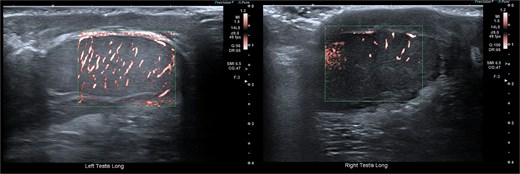

Although testicular torsion is a clinical diagnosis, we felt that the complexity of this case warranted ultrasound, which was immediately available and demonstrated no vascular flow to the left testis and normal perfusion to the right (Fig. 2). Given these findings and suspicion of torsion, emergency exploration was undertaken at our rural facility under paediatric surgical advice obtained from a tertiary centre.

Pre-operative ultrasonographic image demonstrating left and right intracanalicular testis. The left testis has absent colour Doppler flow and heterogeneous echotexture concerning for compromised perfusion.